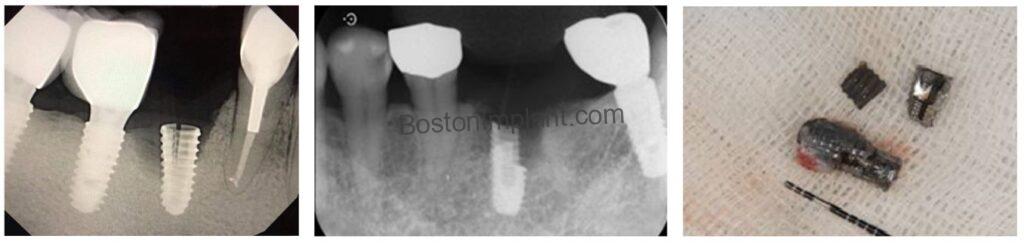

As illustrated in the image above, tissue-level implants feature an additional coronal portion that resides at the gingival level. This design makes them longer and wider at the top compared to bone-level implants. This seemingly small difference significantly impacts implant longevity. I will explain the two key advantages of tissue-level implants for long-term success.

Consider the bone-level implants. Their connection is located at the bone level. Despite manufacturers’ efforts to create a seamless connection, a microscopic gap invariably exists between the implant fixture and the abutment. This microgap can become a niche for plaque and bacteria accumulation, potentially migrating along the connection and ultimately causing bone loss around the implant fixture.

Now, let’s examine the tissue-level implants. Their connection is situated at the gingival level. Even if plaque accumulates in this area, its supra-gingival (above the gum) location makes it more accessible for effective patient cleaning. Furthermore, the connection being at the gum level effectively creates a seal at the bone level. Consequently, the incidence of peri-implantitis with tissue-level implants may be lower compared to bone-level implants.

Finally, the connection design presents another key difference. The connection of bone-level implants is situated below the gum line, making visual confirmation of a precise abutment-implant fit challenging. This can sometimes lead to unnoticed misfits. (As illustrated in the green circle in the image below, a gap can exist between the abutment and the implant.)

Conversely, the platform of tissue-level implants is located at the gum level, facilitating a clinically easier and more accurate assessment of the abutment fit.